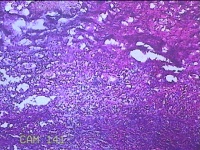

性别

男

年龄

32岁

临床诊断

1.急性化脓性阑尾炎并穿孔 2.弥漫性腹膜炎

一般病史

转移性右下腹疼痛1天。

标本名称

阑尾

大体所见

灰白暗红色阑尾4.8x1.3x0.7cm一条,表面糜烂,肿胀,带少许系膜,切断阑尾,见腔内暗红色。